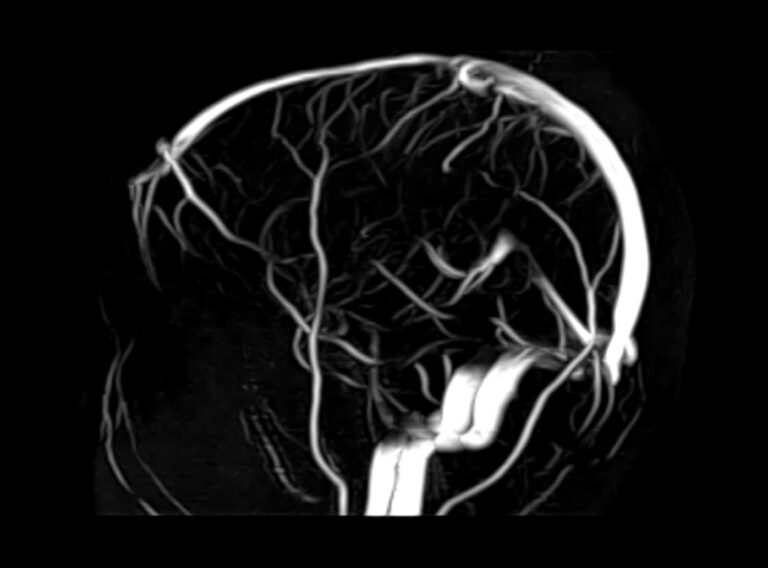

Для диагностики поражения черепно-мозговых нервов, а также оценки состояния окружающих их тканей и визуализации сосудистой сети головного мозга в клинике «Доступная медицина» проводится комплексное обследование МРТ головного мозга + Мр-ангиография головного мозга + МР-венография головного мозга + черепно-мозговые нервы. Данное обследование включает в себя несколько протоколов: стандартный – для оценки состояния всех структур головного мозга и дополнительные – для изучения очагов поражения черепных нервов и визуализации всей сосудистой системы головного мозга.

Исследования выполняются на современном высокопольном томографе экспертного класса TOSHIBA VANTAGE TITAN 1,5 Тесла, который использует разные режимы сканирования с толщиной среза от 1мм в различных плоскостях с последующей цифровой обработкой полученных данных для создания трехмерных изображений. МР-ангиография отображает состояние артериальной системы кровоснабжения головного мозга. МР-венография головного мозга позволяет детально изучить особенности венозного русла головного мозга.

Компьютерная программа обрабатывает данные, полученные при сканировании, и формирует объемные изображения как самого мозга, так и сосудистой системы в отдельности без прилегающих тканей. Методики применяются одновременно и взаимодополняют друг друга.